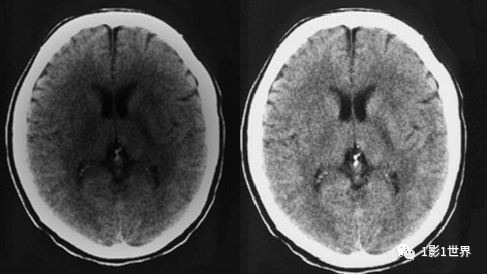

,避免密度对比过大的物体相接触。部分容积效应,是影像断层扫描中的一个概念,因为层厚的影响,相邻组织间出现重叠,表现出异常影像。